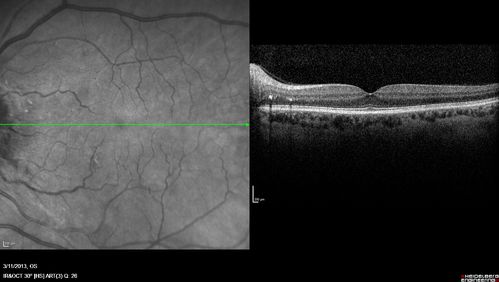

Malignant Hypertension - Cotton Wool Spots - Elschnig Spots - Optic Nerve Edema

Hypertensive Retinopathy - Cotton Wool Spots and Elschnig Spots and Optic Disc Edema - Malignant Hypertension